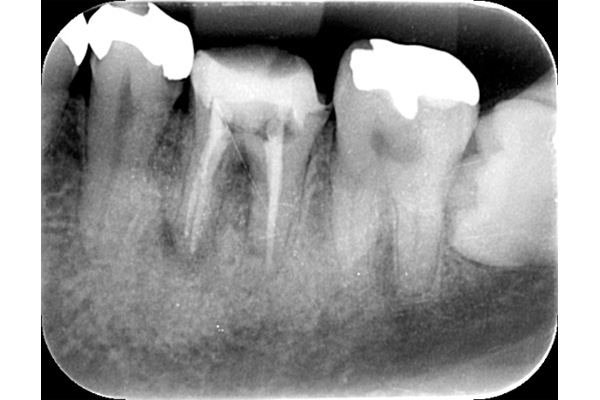

根の先に膿が溜まっています。

根の中の清掃を行い、防腐剤を詰めました。

膿の塊がなくならないため、根の先を切り取りました。と同時に膿の塊も取り除きました。

1ヶ月後。根の先の膿がなくなったことと、根の先端を切り、感染物質がなくなったことで、骨の再生が始まっています。